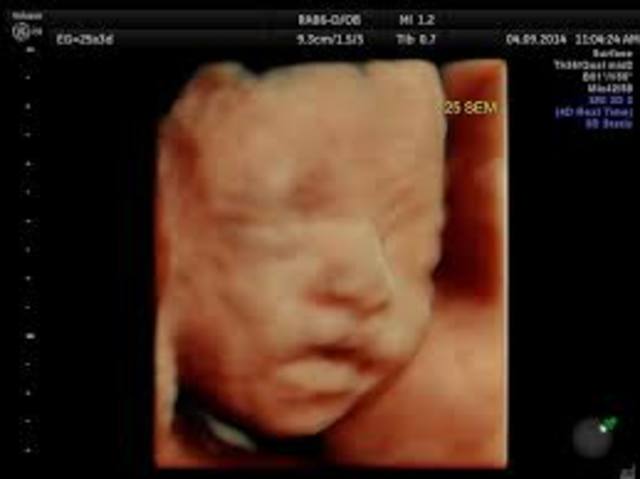

sabemos que a las 25 semanas de embarazo el niño ya tendrá pestañas. Sin embargo, el color de los ojos no se desarrolla por completo. Esto se debe a que algunos pigmentos necesitan luz para acabar de formarse. De hecho, los ojos de tu bebé pueden cambiar en las primeras semanas de vida. Los asiáticos y los africanos nacen con ojitos marrones o grises y acaban teniéndolos oscuros o negros.

A partir de la semana 26 de embarazo el pequeñín hará sus primeros gestos y arrumacos. Igualmente, empezará a hacer uso de más reflejos importantes como el reflejo labial de succión, dado que empieza a chuparse el dedo con virulencia. La mayor parte del día, tu bebé estará durmiendo.

Alrededor de las 27 semanas de embarazo se podrán escuchar los latiditos del bebé poniendo los oídos sobre tu abdomen. Debes saber que tu ritmo cardíaco está muy vinculado al de tu hijo y tu estrés y tus hábitos le influyen directamente. Si no llevas unas costumbres y un ritmo de vida sanos, puede desarrollar diversos problemas.